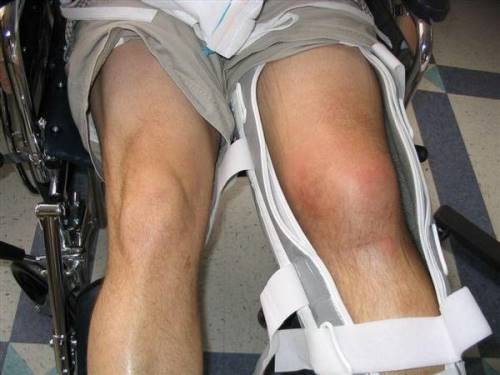

- колено деформировано, меняется его форма, при переднем или заднем вывихе колено напоминает ступеньку, а при боковом – нога ротирована внутрь или кнаружи;

- нога выглядит укороченной;

- при повреждении кровеносных сосудов развивается кровоизлияние в полость сустава – гемартроз;

- травма сосудов сопровождается отсутствием пульса на ноге, похолоданием, онемением и посинением ноги;